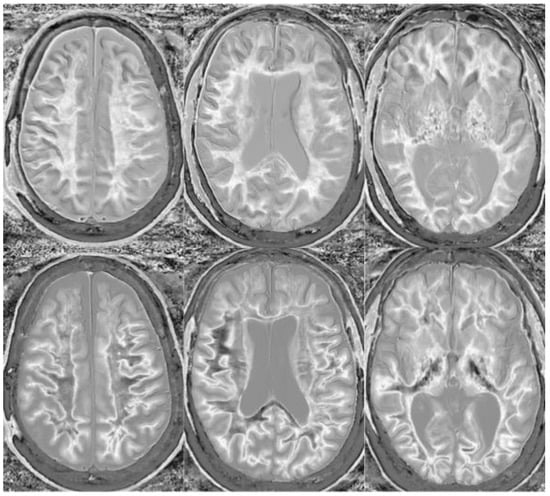

Figure 18.

Divided Subtracted Inversion Recovery (dSIR) in a patient methamphetamine user. Narrow middle domain dSIR images at the level of the centrum semiovale (left), corona radiata (middle), and basal ganglia (right) in a volunteer immediately after a methamphetamine binge (top row) and 4 months into abstinence (bottom row) TIshort = 350 ms. TIlong = 500 ms. TE = 7 ms, TR = 5000 ms. The top row images show the “white out” sign, indicating diffuse mild white matter T1 elevation. The signal in the white matter partially normalizes on the bottom row. The appearance is closer to intermediate than normal, but there is definite improvement.